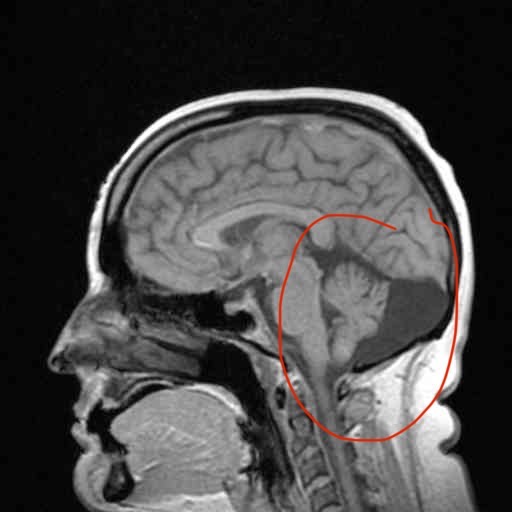

My name is Kayla and I am a disabled veteran who needs some help. I was just diagnosed with a brain cyst and need surgery. I lost my full-time job in August due to debilitating migraines that I get 3-4 times a week. I am in and out of the ER as this cyst is pushing on my brain, causing so many issues. I meet with a surgeon on January 8th. We struggled to get last month's rent paid but were able to do it.